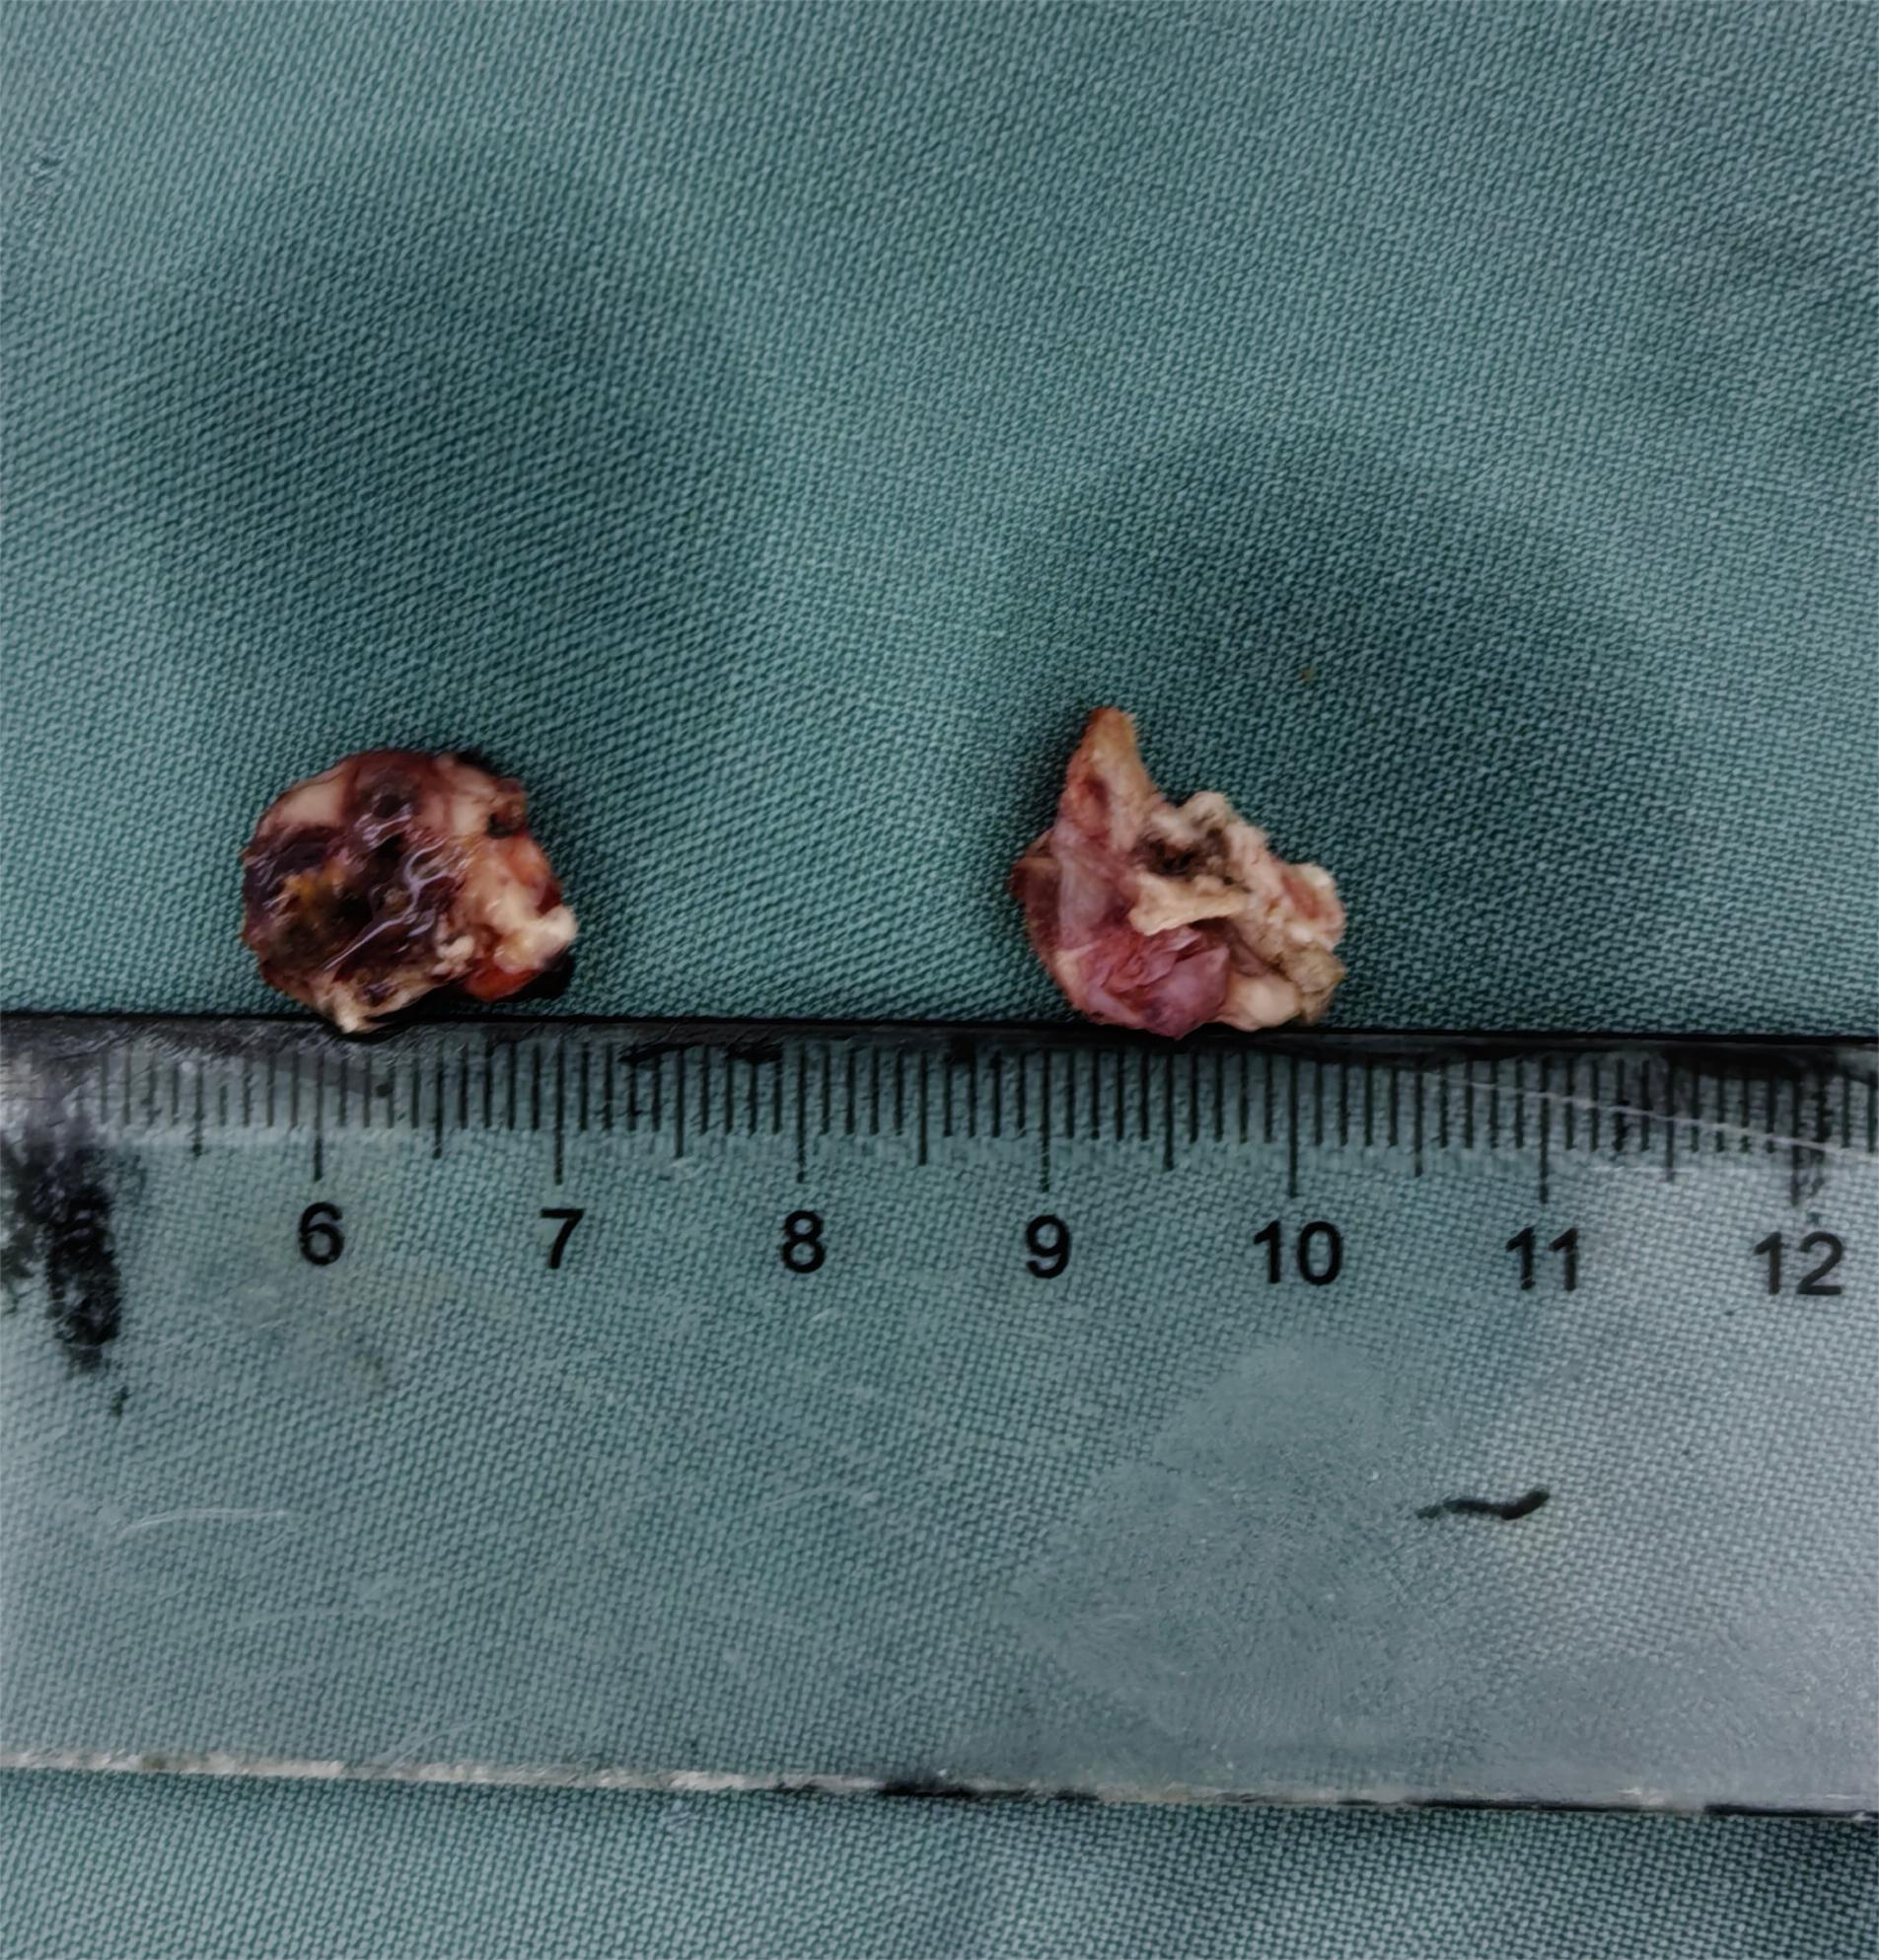

术中情况

术后资料